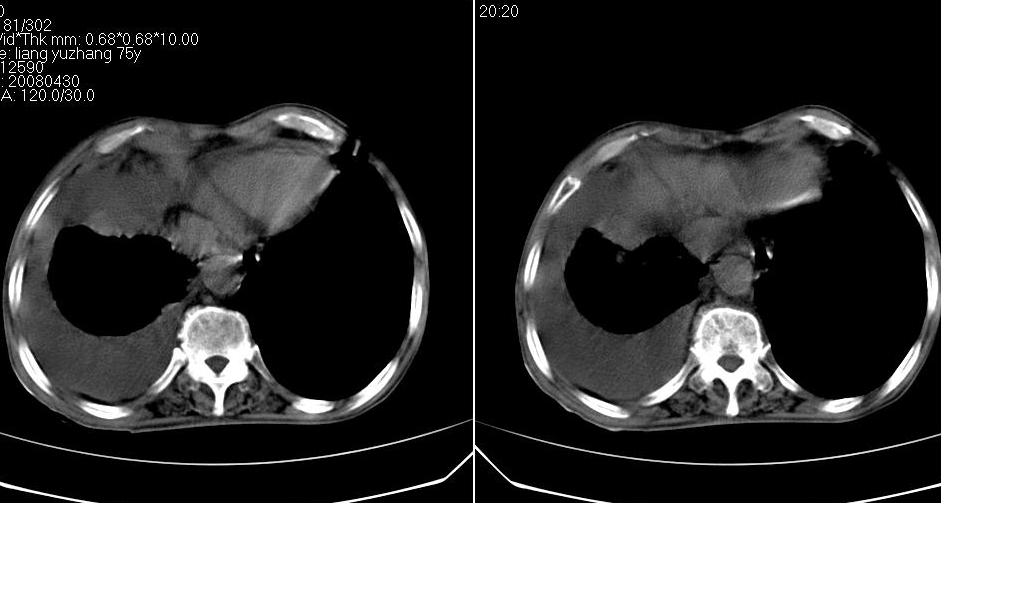

以下是引用zsl6918在2008-5-3 19:53:00的发言:[br]右肺中心型肺癌并纵隔淋巴结转移,胸膜转移,右肺癌性淋巴管炎。

以下是引用liuyue在2008-5-3 20:49:00的发言:[br]1.右侧中心型肺癌伴双肺转移瘤、纵隔淋巴结转移、右侧胸腔积液(侵及胸膜所致可能性大)。[br]2.右肺阻塞性肺炎,癌性淋巴管炎不除外。

以下是引用mzh123在2008-5-3 21:12:00的发言:[br]本人持有不同观点[br]1、右肺似有团块表现,但只有一个层面,所以本人认为还是以片为主,所以不能首先考虑肿瘤[br]2、右肺普遍成纤维化改变 并伴有片状炎症改变,和癌性淋巴管炎表现不同[br]3、所以本人认为是间质纤维化伴感染可能大 及胸腔积液